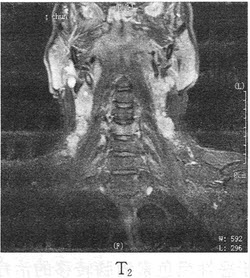

22������ѡ����

�����У�58�ꡣ��������2�����࣬X��ͼ�����£����п��ܵ�����ǣ���

A.ʳ�ܰ�

B.ʳ�ܾ�������

C.ʳ�ܼ�����

D.����ʳ����

E.ʳ�ܽ��